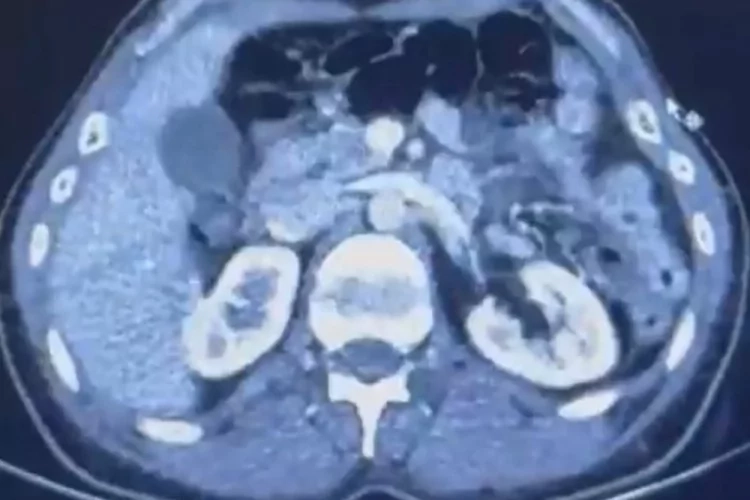

Edinilen bilgiye göre Narkotik Suçlarla Mücadele Şube Müdürlüğü ekiplerince uluslararası uyuşturucu madde ticareti yapan kurye şahıslara yönelik gerçekleştirilen çalışmalarda, İran'dan Türkiye'ye uyuşturucu madde getirdiği tespit edilen şüpheli şahısların yakalanması amacıyla operasyon düzenlendi. Düzenlenen operasyonda; S.C., R.B.C. ve G.M. yakalandı. S.C. ve R.B.C.'nin Kayseri Şehir Hastanesi'nde yapılan iç beden muayenelerinde, mide kısımlarında bulunduğu tespit edilen 50 adet kapsül şeklinde toplam 554 gram uyuşturucu madde ele geçirildi. Şüpheliler gözaltına alınarak haklarında 'Uyuşturucu Madde Ticareti Yapmak' işlem başlatıldı.